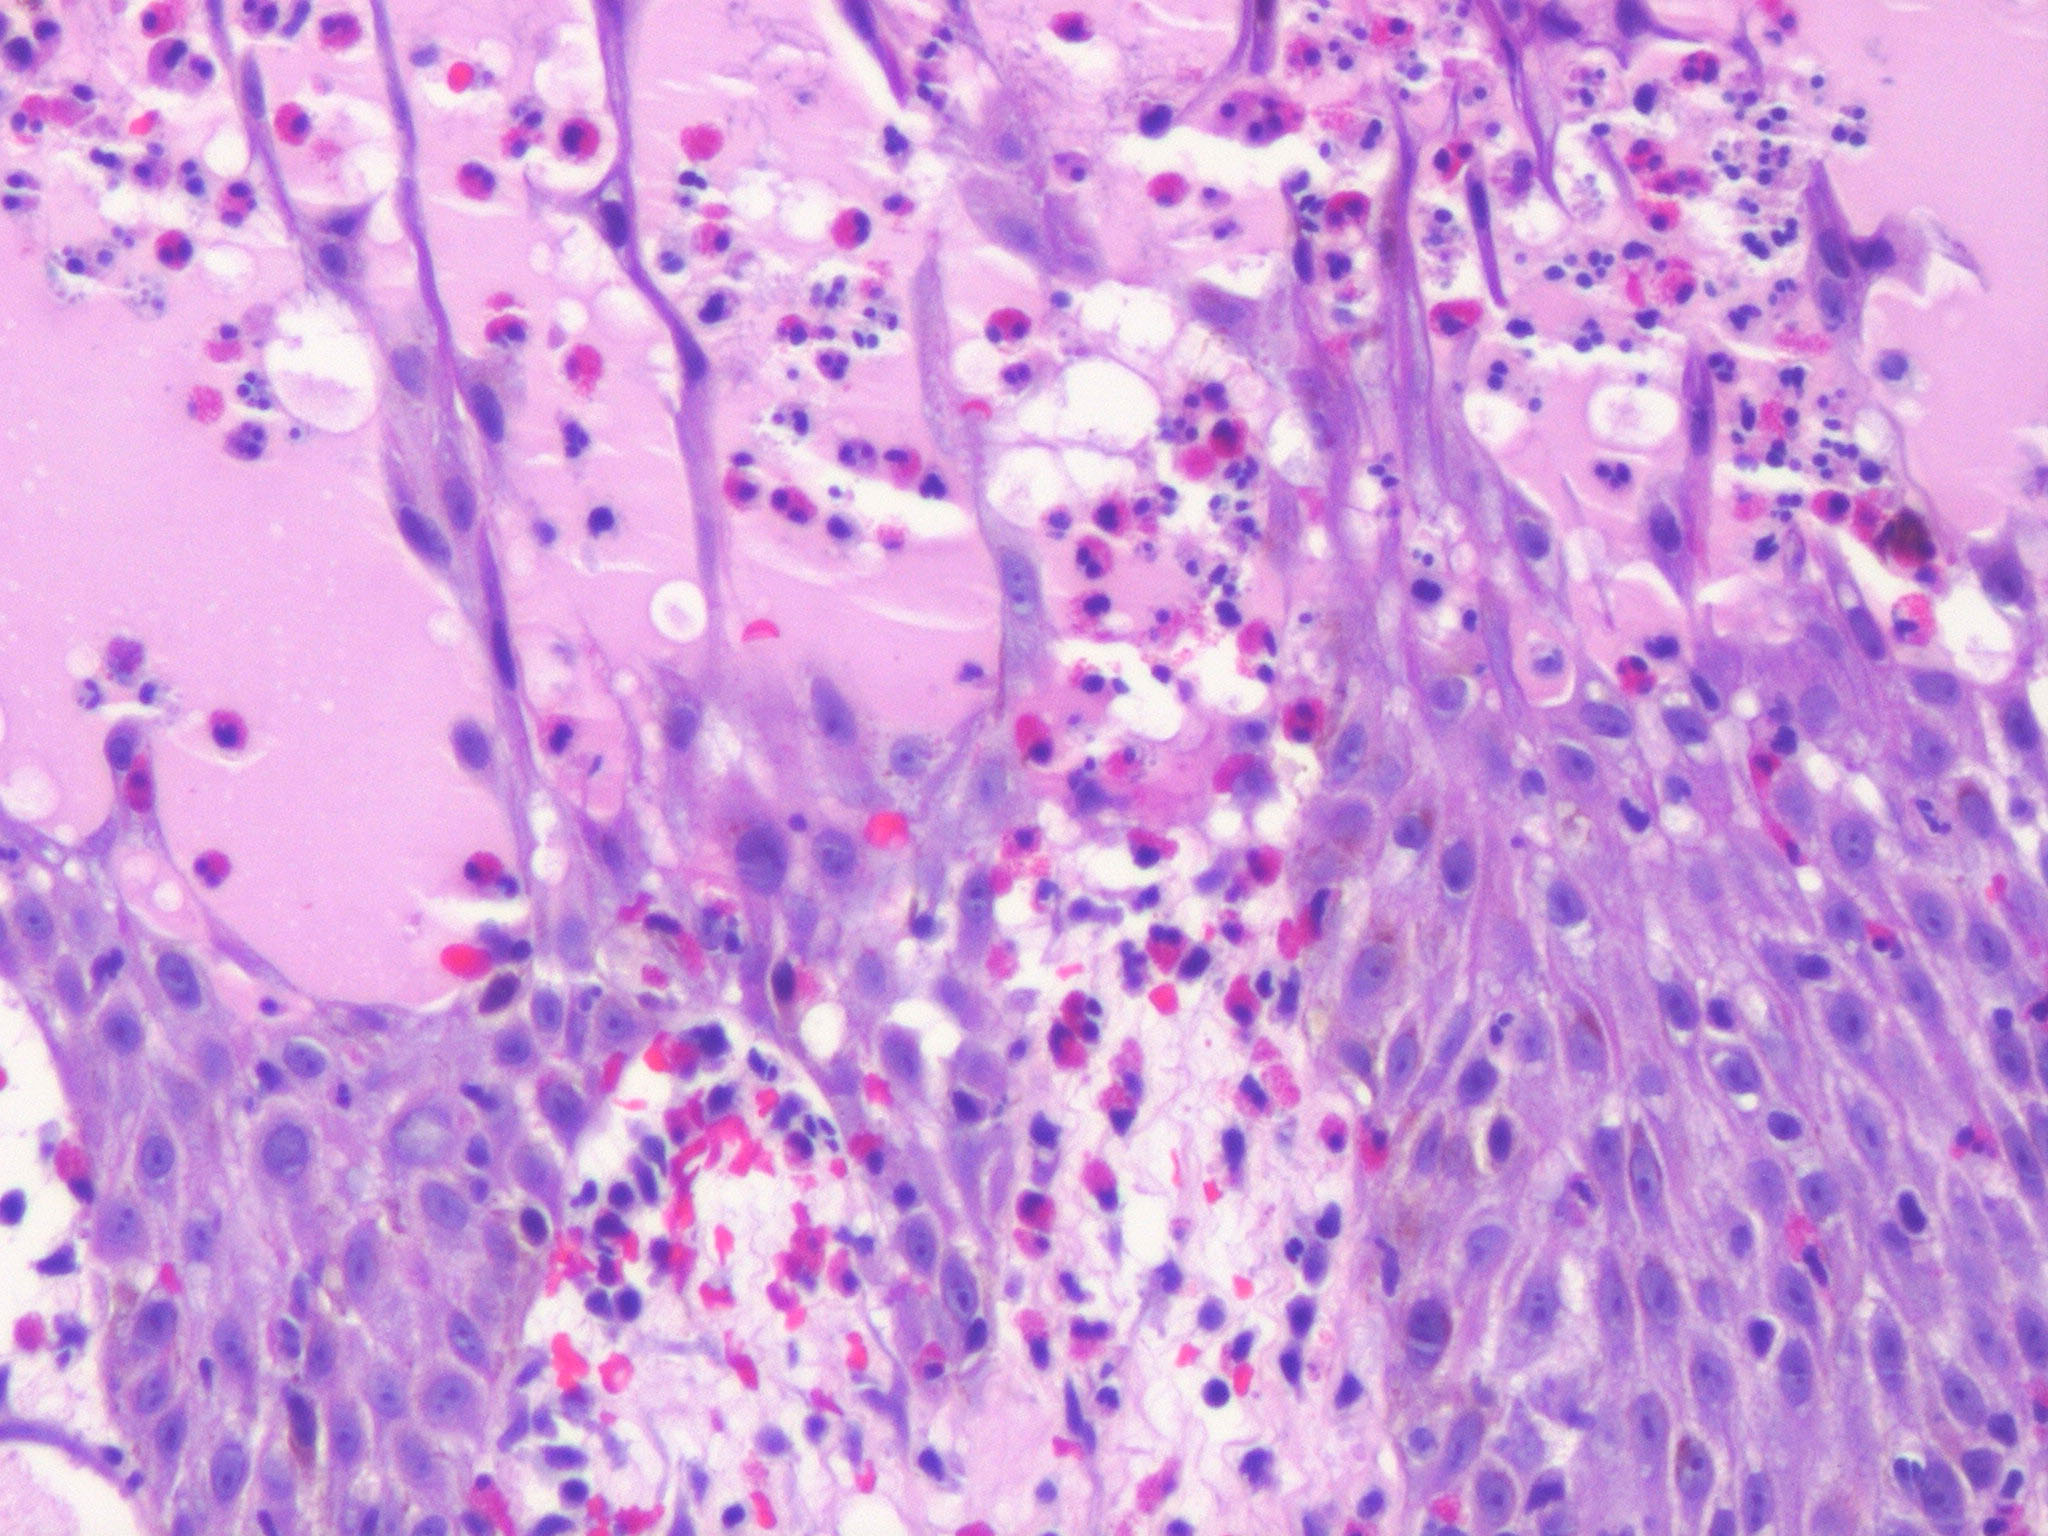

Acute contact dermatitis = التهاب ا لجلدالحاد بالتماس